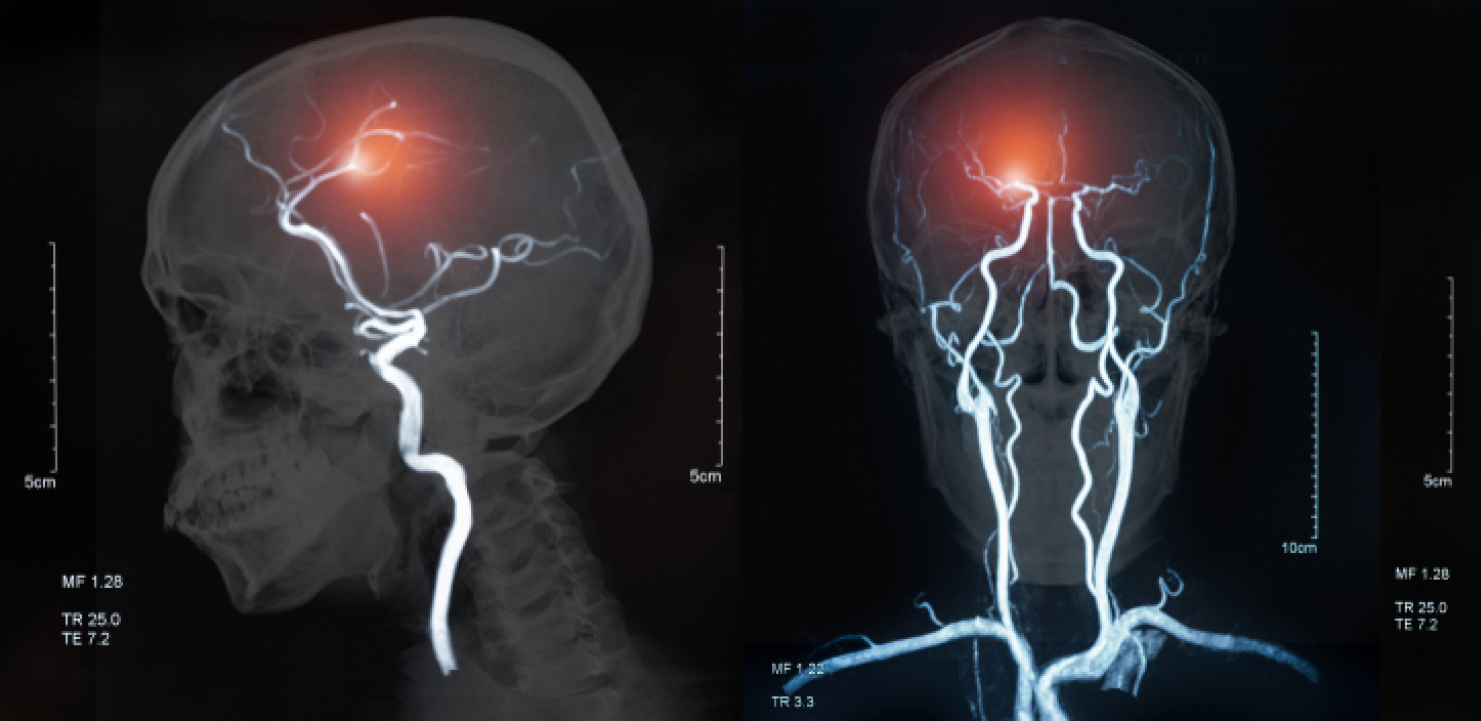

Bila je voljna da pokuša nešto ekstremno: ugraditi elektrode u njen mozak kao deo eksperimentalne terapije. Istraživači kažu da bi tretman - duboka moždana stimulacija ili DBS - mogao na kraju pomoći milionima u depresiji koja se opire drugim tretmanima.

Tretman daje pacijentima ciljane električne impulse, slično kao pejsmejker, ali za mozak. Sve veći broj istraživanja obećava, dok je par njih još uvek u toku, uprkos tome što su dve velike studije koje nisu pokazale prednost upotrebe DBS-a za depresiju privremeno zaustavile napredak.